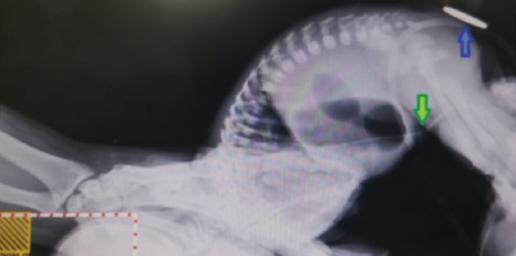

Se coloca en cuna radiante a 37 °C con oxígeno libre a 2 l/min. En la exploración se encuentra permeabilidad de coanas, reflejos primitivos presentes, tórax y abdomen sin compromisos, cadera estable, llenado capilar de 3 segundos, fontanela anterior de 1 cm aproximadamente y posterior parcialmente cerrada; no se encuentra fosa anal (Fig. 1) y existe impedimento para el paso de la sonda orogástrica. Se realiza una radiografía toracoabdominal anteroposterior que evidencia una imagen característica en cuádruple burbuja y ausencia de aire distal, que hace sospechar atresia intestinal (Fig. 2). Ante estas alteraciones, se decide trasladar a la paciente a nuestra institución pública.

Se solicita invertograma para determinar la altura del cabo colónico; sin embargo, la probable presencia de atresia duodenal o yeyunal no permite una correcta valoración (Fig. 3). La búsqueda de células meconiales en orina fue negativa.

Figura 3 Invertograma que muestra la altura proximal de la columna de aire (flecha verde) y el sitio anatómico del orifico anal (flecha azul).